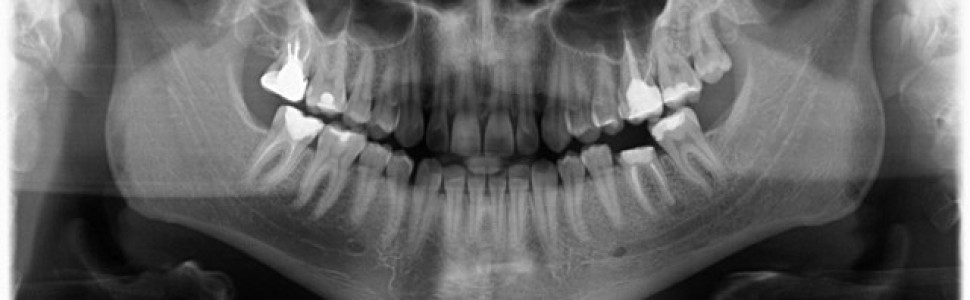

Wykonano pantomogram oraz zdjęcie celowane, które ujawniło zmianę okołowierzchołkową przy korzeniu dystalnym. Nie stwierdzono patologii tkanek twardych zębów sąsiadujących z zębem zakwalifikowanym do ekstrakcji, dlatego powzięto decyzję o odbudowie implantologicznej przyszłego braku zębowego (ryc. 1-3).

Ryc. 2. Zdjęcie pantomograficzne wykonane przed zabiegiem. Ryc. 3. Zdjęcie zębowe zęba 36.